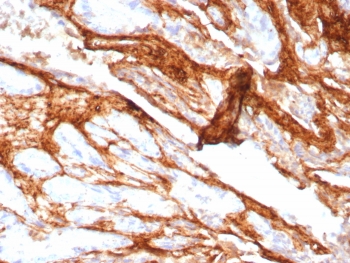

IHC staining of FFPE human prostate carcinoma tissue with Decorin antibody (clone DCN/8760R). HIER: boil tissue sections in pH 9 10mM Tris with 1mM EDTA for 20 min and allow to cool before testing.